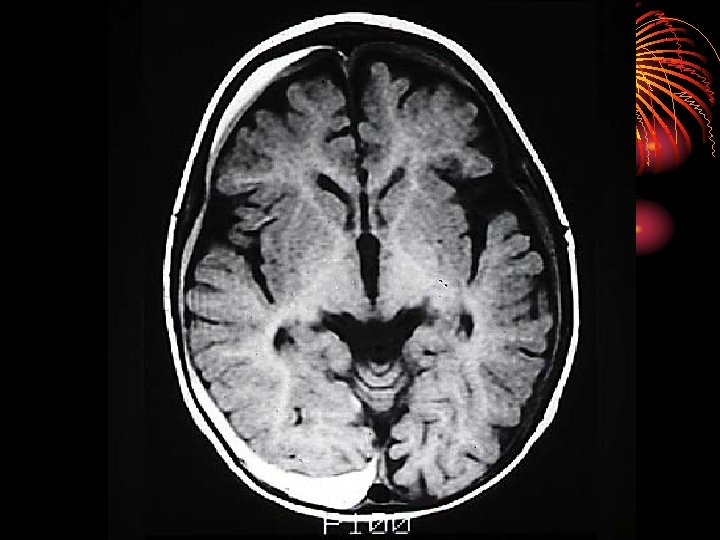

• Magnetic Resonance Imaging (MRI) • A technique that uses magnetic fields and radio waves to produce computergenerated images that allow us to see structures within the

• The CEREBRAL CORTEX is the intricate, wrinkled covering of the brain (FISSURES) (actually a bump is a gyrus and a groove is a sulcus – but that’s a bit too much info…) • In addition to interneurons, it contains GLIAL CELLS, which guide neural connections, provide nutrients to myelin, and mop up neurotransmitters

• The two hemispheres of the brain are connected by the CORPUS CALLOSUM

• The Cerebral Cortex is split into four LOBES, with half of each one on the left, and half of each one on the right: • The FRONTAL LOBE PARIETAL LOBE OCCIPITAL LOBE TEMPORAL LOBE